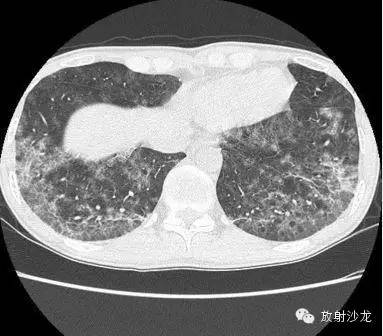

两周后的CT和X线:

胸片示两肺中下野边界不清的磨玻璃样阴影(GGO)。CT示两肺地图样分布的GGO,主要位于两肺上叶、右肺中叶及两肺下叶,其中两肺下叶多发的GGO融合并伴有小叶间隔增厚。2周后随访胸片示双肺野弥漫分布的GGO增多。患者第一次就诊时未告知自己的性取向。只告知了曾接触过染发剂。患者按肺间质性疾病给予激素治疗。然而,治疗后患者的症状和影像学表现均加重。患者血液检测结果显示艾滋病病毒阳性。支气管肺泡灌洗液GMS染色示大量的卡氏肺孢子虫。